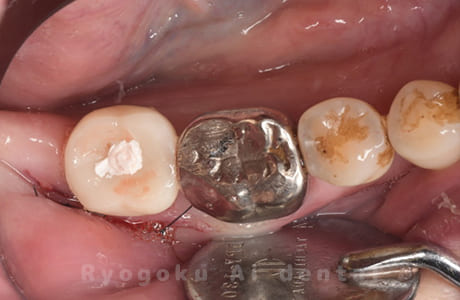

Case12

-

- 原因

- 左下7番歯牙破折

- 治療内容

- インプラント治療

- 治療費用

- 約600,000円

左下の奥歯が痛いとのことでご来院された患者様です。歯が完全に割れており、保存が不可能であったため、抜歯を行い、その際に骨に変わるお薬を入れ、十分な治癒を待ってからインプラント治療を行いました。経過良好で、大変満足されました。

<リスク・副作用>

治療後、痛みや違和感、出血、腫れなどが出る事があります。喫煙者、糖尿病などの方の場合、歯が生着しない場合があります。